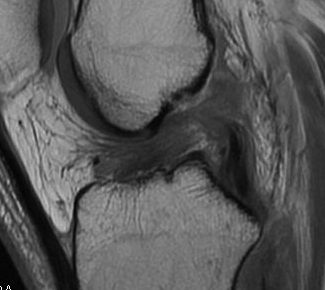

Torn ACL on MRI

Findings

- high signal intensity / oedema in ACL, especially acutely

- unable to identify continuous fibres from tibia to femur

- loss of taut, straight line of fibres

Sagittal T2 MRI with midsubstance ACL tear Sagittal T1 MRI with midsubtance ACL tear

Sagittal MRI with complete ACL rupture